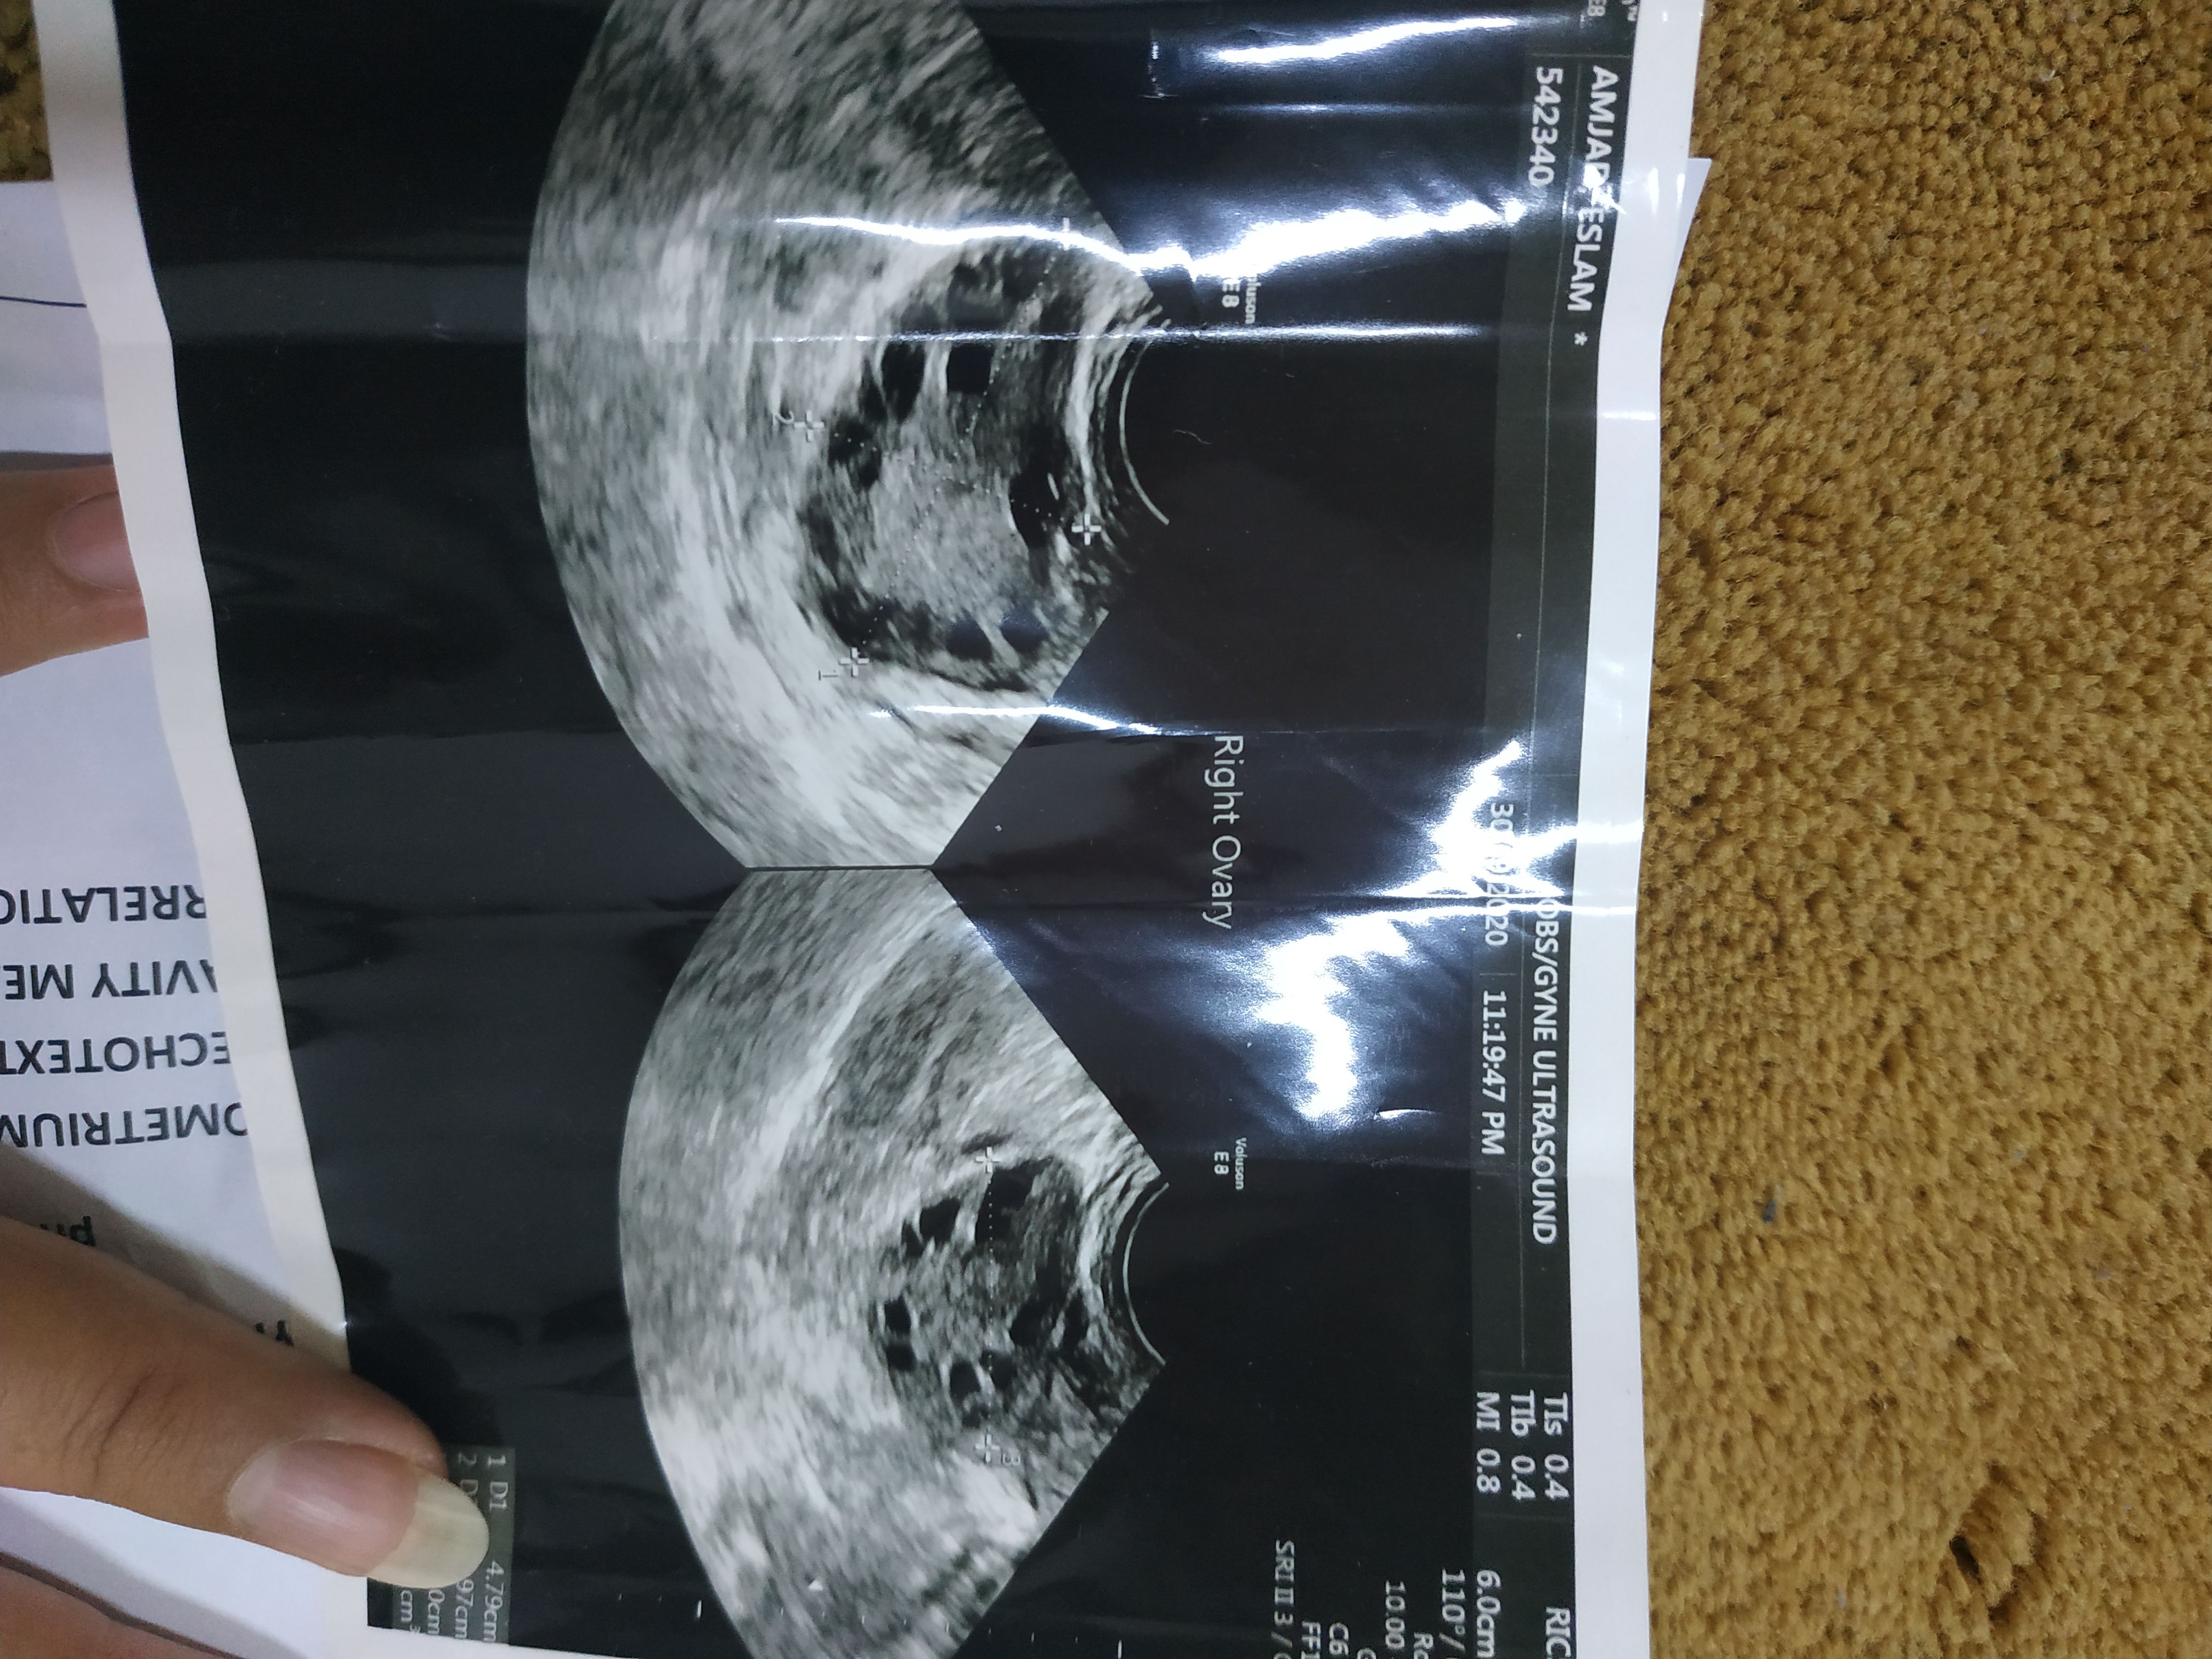

Latest ultrasound report

Ultrasound report

Ultrasound